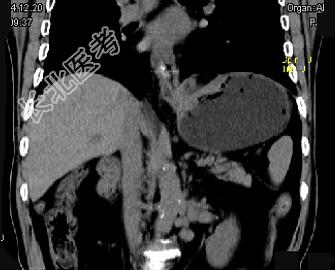

- 单项选择题男,75岁, 吞咽有梗阻感,消瘦、乏力、中上腹痛, 影像检查如图,最可能的诊断是 ( )

A、食管癌

B、胃窦癌

C、贲门癌

D、慢性胃炎

E、胃淋巴瘤